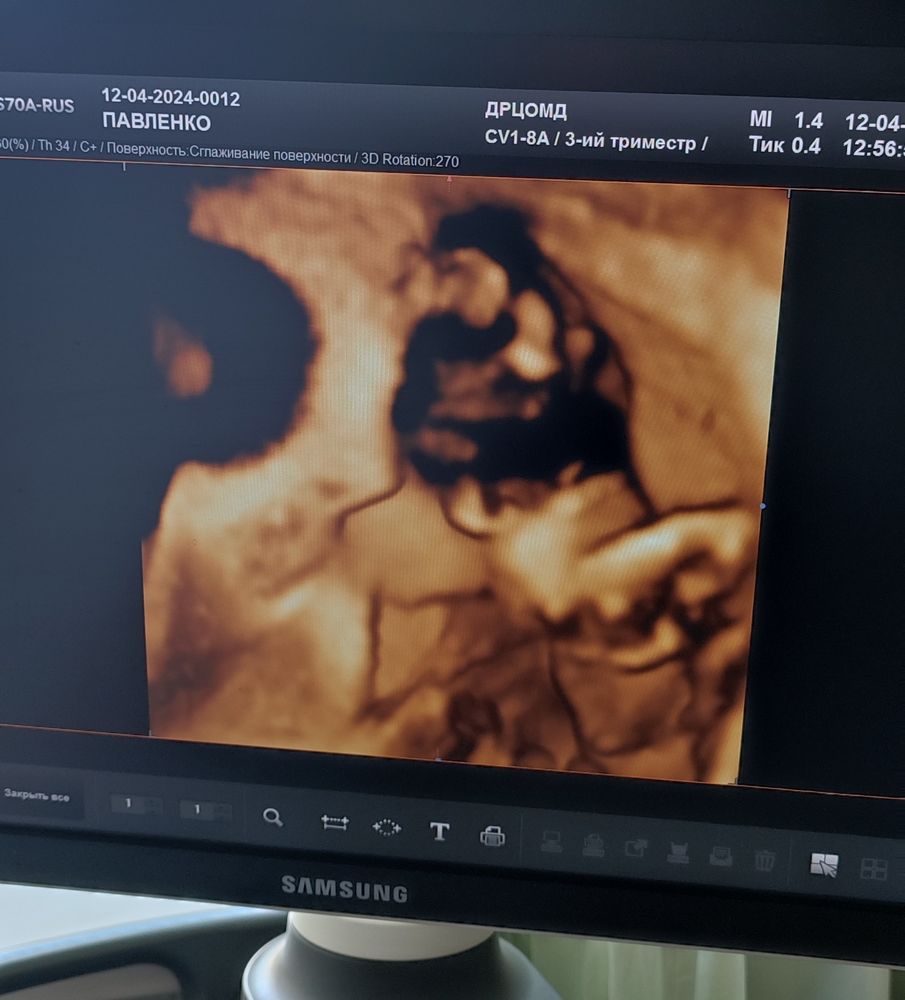

Были в пятницу на УЗИ, из-за сниженного маточного кровотока смотрим как там сыночек наш растёт.

Растёт, вес 2200. "Он у вас такой стесняшка", - сказал Олег Геннадьевич, когда я попросила хоть какое-нибудь фото.

Хоть какое-нибудь получилось😅

Фото-расшифровка:

Фото без расшифровки:

В общем, показал нам мужичка😄 довольно расстроенного, потому что вторглись в его личное пространство)))